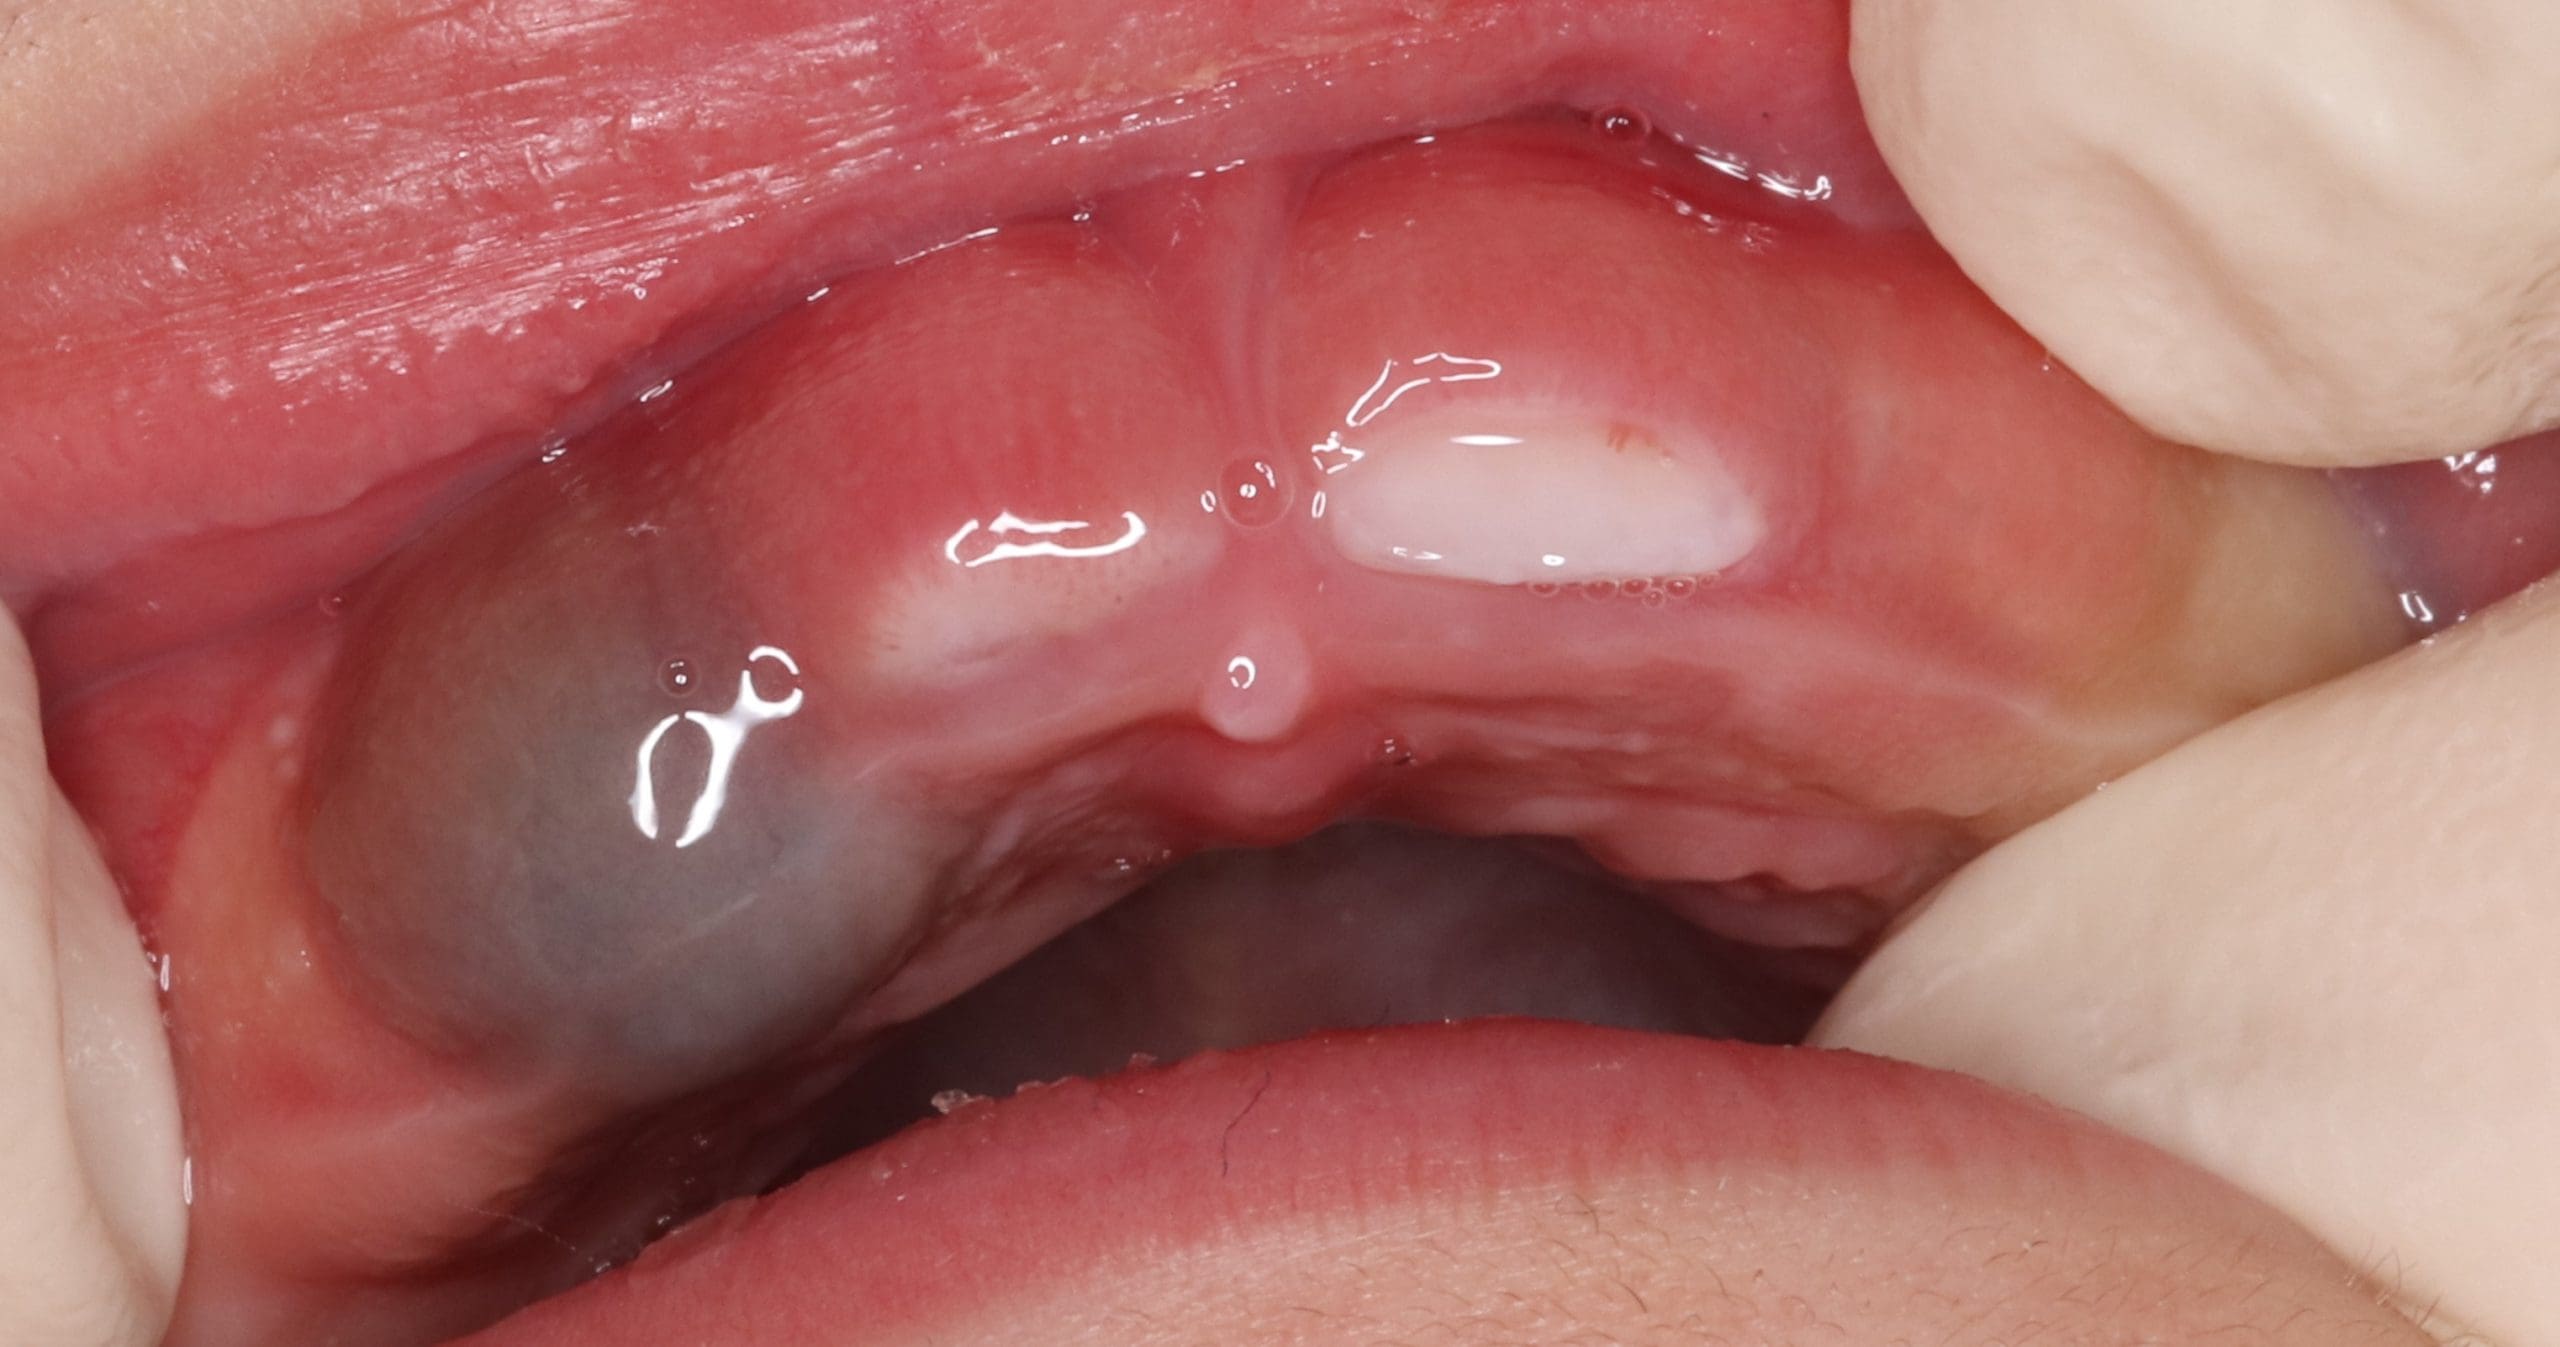

Eruption Hematoma

Eruption hematomas are usually found in children. The fluid in the cyst is sometimes clear creating a pale-coloured cyst although often they are blue. An eruption cyst (eruption hematoma) is a developmental soft-tissue cyst of odontogenic origin that forms over an erupting tooth . Common in children while rare in other ages and found in both dentitions, baby and adult teeth.

If your child has an eruption hematoma, you should bring them to the dental office where the doctor will examine and decide if treatment is required.